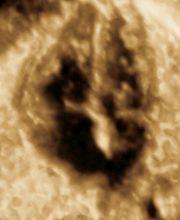

Produktinfos Die Pränatalmedizin ist die vorgeburtliche Medizin (lat. prae- = vor, natus = Geburt), die sich sowohl auf die Schwangere als auch auf den Embryo bzw. den Fötus bezieht. Zur Pränatalmedizin gehören: Pränatale Diagnostik (Erkennen von kindlichen Störungen im Mutterleib) Pränatale Therapie (Behandeln der Mutter und des ungeborenen Kindes) Wir sind ein von der DEGUM und dem GBA zertifiziertes Zentrum, das das gesamte Spektrum des Fachs auf höchstem Niveau anbietet, kurz: Vom ersten Herzschlag bis zur Geburt: Vorgeburtliche Mitbetreuung aus einer Hand In der Pränatalen Diagnostik bieten wir alle Verfahren mit High-End-Geräten der neuesten Generation an: Ersttrimesterschall, Fehlbildungsschall, fetale Echokardiographie, Dopplersonographie, 3D/4D-Ultraschall sowie Punktionen der Fruchthöhle (z.B. Amniozentese, Chorionzottenbiopsie). Auch die cffDNA-Tests sind bei uns bereits fest etabliert. Zum Glück ergeben unsere speziellen Untersuchungen in den meisten Fällen unauffällige Befunde. Wenn es aber leider nicht so sein sollte, lassen wir Sie nicht im Stich. Wir werden Sie in jeder Situation umfassend informieren und begleiten, auch unter Hinzuziehung weiterer ärztlicher Spezialisten. Diese kommen in die Praxis und nehmen an der Ultraschalluntersuchung teil. So kann umfangreich beraten werden, und die spätere Therapie geht Hand in Hand. Zusätzlich legen wir Ihnen besonders in diesen Situationen eine psychosoziale Beratung nahe und vermitteln auf Ihren Wunsch den Kontakt. Unsere Praxis liegt verkehrsgünstig direkt an der A7, Ausfahrt Othmarschen. Ebenso sind wir mit öffentlichen Verkehrsmitteln gut zu erreichen (S1, Metrobus 1). Hierüber besteht auch eine gute Verbindung zur Fernbahn und zum Airport. Wir freuen uns auf Ihren Besuch und wünschen Ihnen eine angenehme Schwangerschaft! Sicherheit für Sie und Ihr Kind Unsere Praxis bietet Ihnen die Kompetenz und Unterstützung die Sie wünschen oder benötigen. Mit modernster Technik besteht heute die Möglichkeit Risiken und Probleme frühzeitig zu erkennen und zu behandeln. Das Team unserer Praxis, bestehend aus Frauenärzten mit der Schwerpunktbezeichnung „Spezielle Geburtshilfe und Perinatalmedizin“ und Humangenetikern, arbeitet auf höchstem Niveau und bietet Diskretion und Vertrauen. Freundlichkeit und Kompetenz sind Teil unseres Verständnisses von Verantwortung. Die passende Begleitung Innerhalb der Pränatalmedizin haben wir uns, neben gängigen 3D-Ultraschall- und Doppler-Ultraschalluntersuchungen, auf die Früherkennung von Fehlbildungen und die Betreuung bei Risikoschwangerschaften spezialisiert. Dazu haben wir uns zum einen auf das erweiterte Ersttrimesterdiagnostik (u.a. mit Nackentranzparenzmessung) spezialisiert sowie gegebenenfalls die weitere Abklärung des Kindes mittels cffDNA-Test, Amniozentese oder Chorionzottenbiopsie. Zum anderen bietet unsere Praxis interdisziplinäre Begleitung bei Zwillings- oder Drillingsgeburten, Fehlbildungen oder Wachstumsverzögerung des Kindes. Unser Praxisteam, die Ärzte für Frauenheilkunde und Geburtshilfe und die Ärzte für Humangenetik, freuen uns auf Sie, Ihr Kleines und Ihre Fragen.